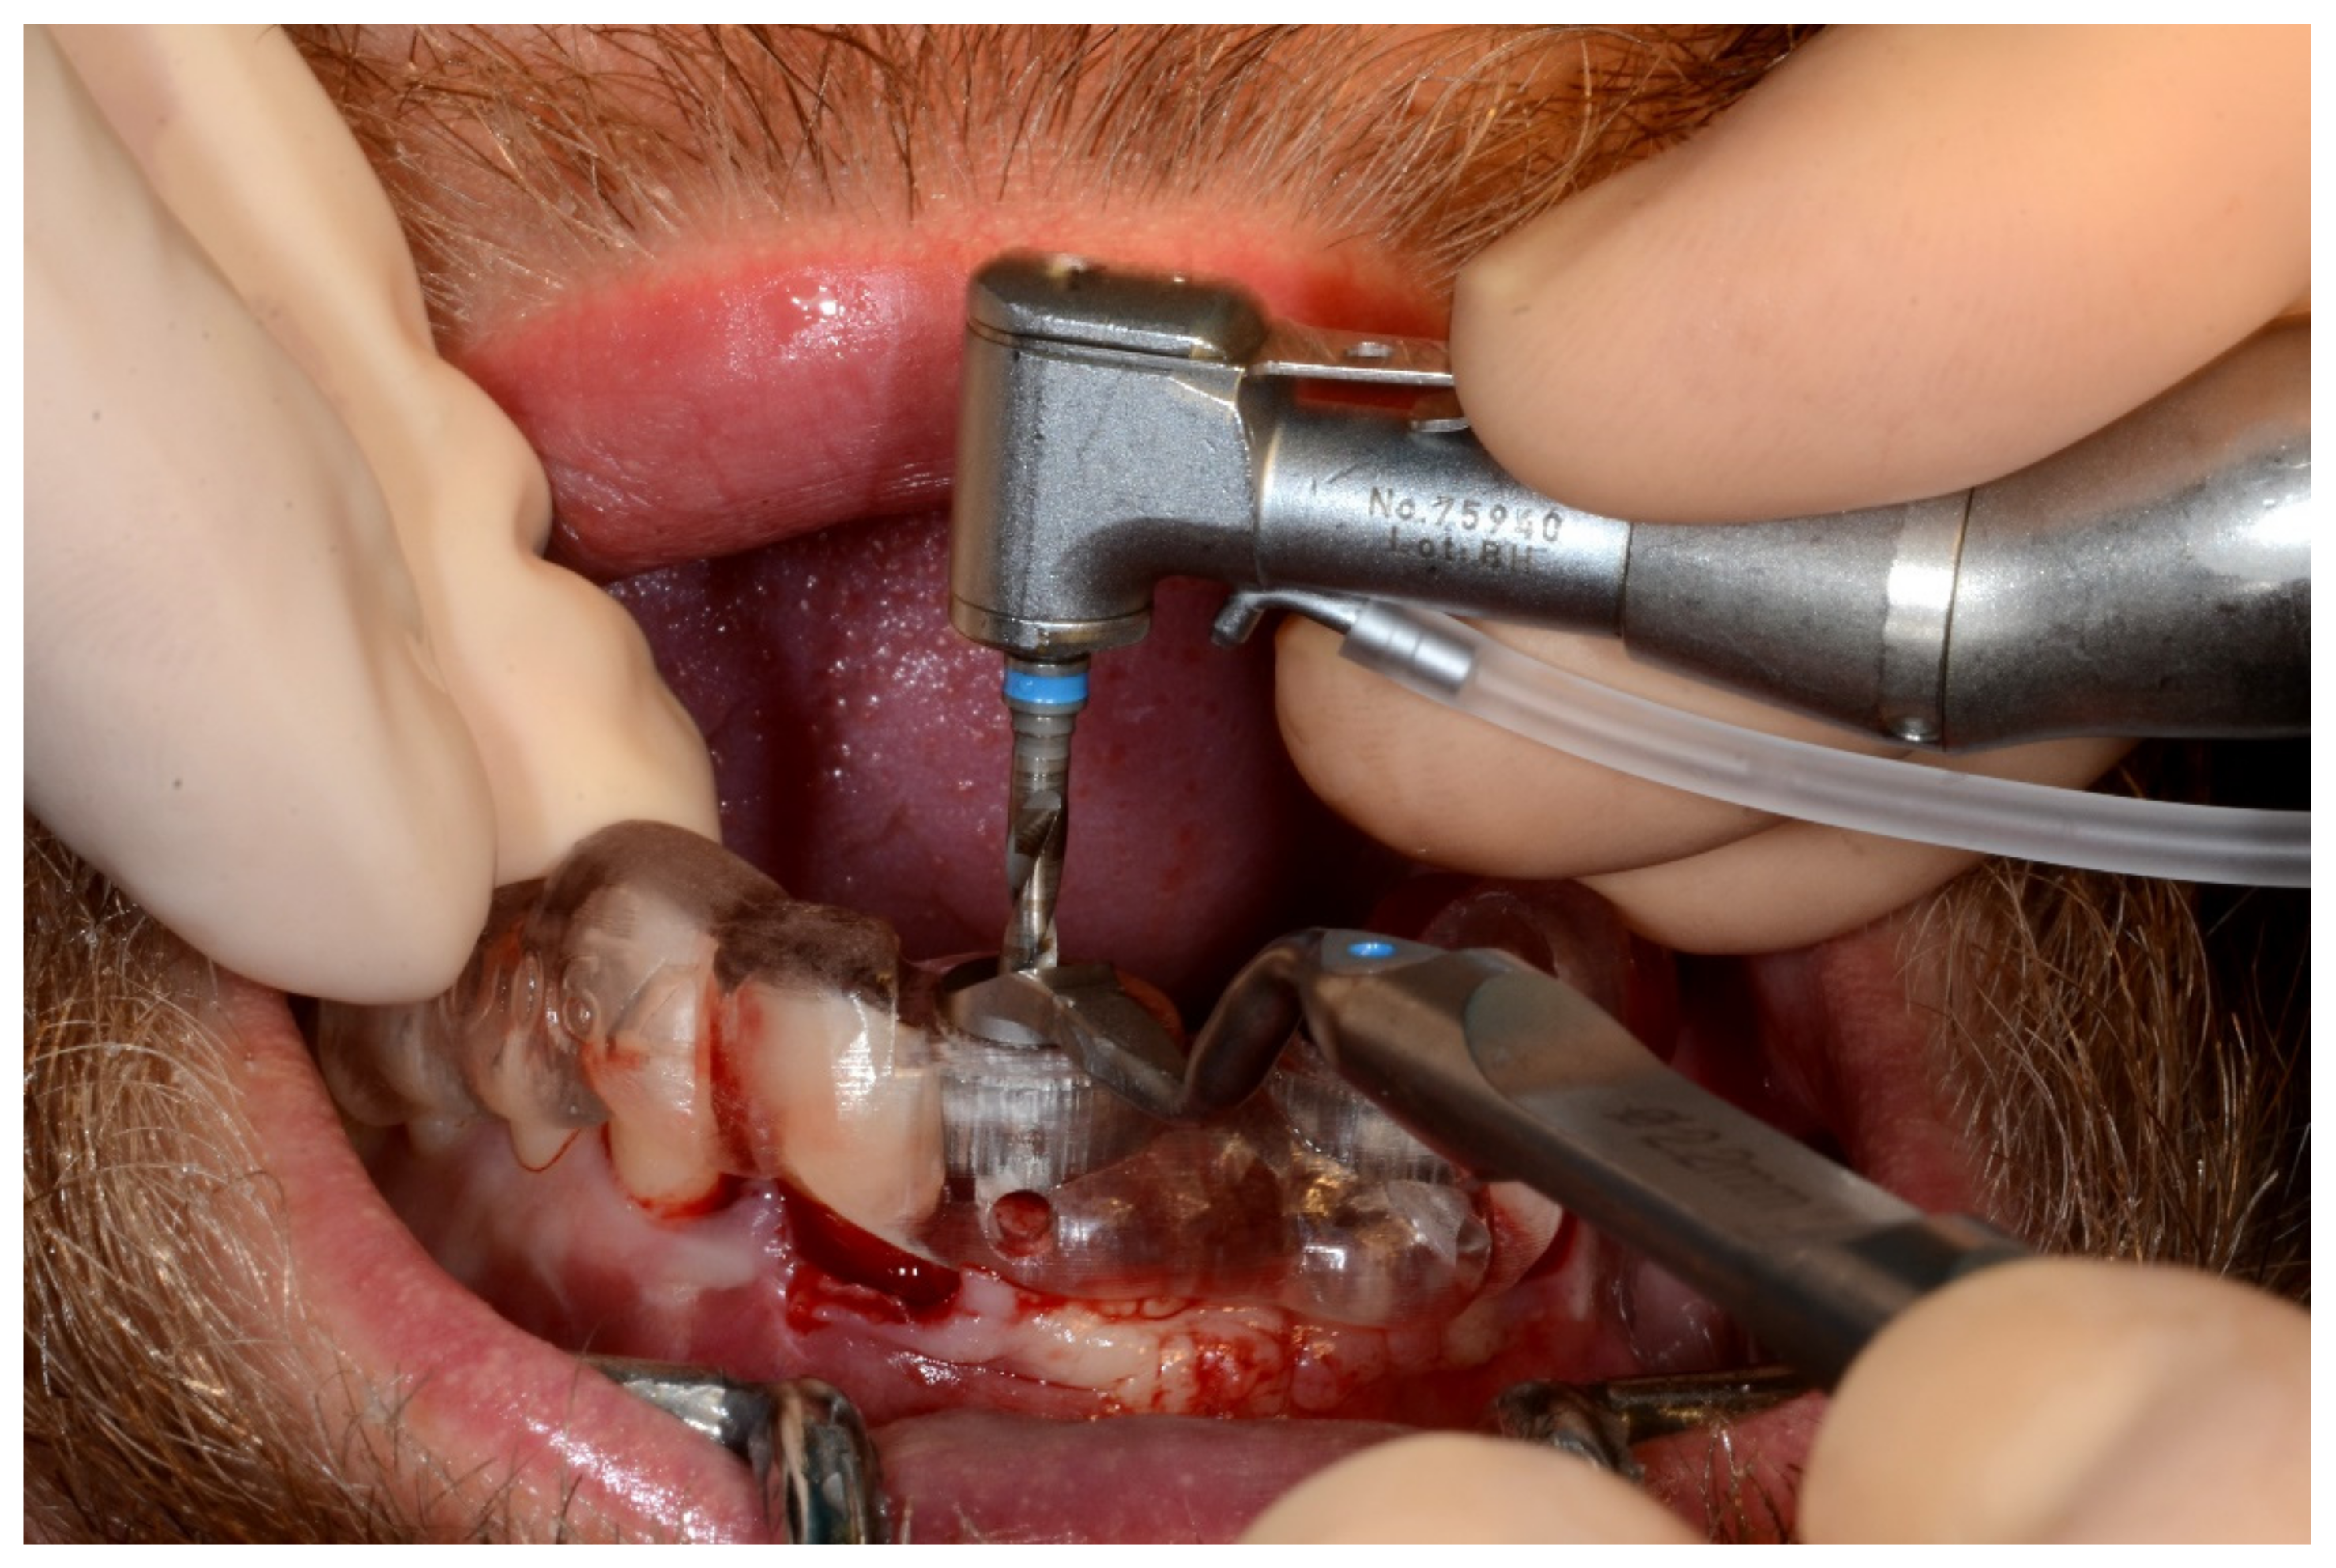

Figure 24.

Implant bed preparation using guided drills inserted into specific ad hoc drill handles.